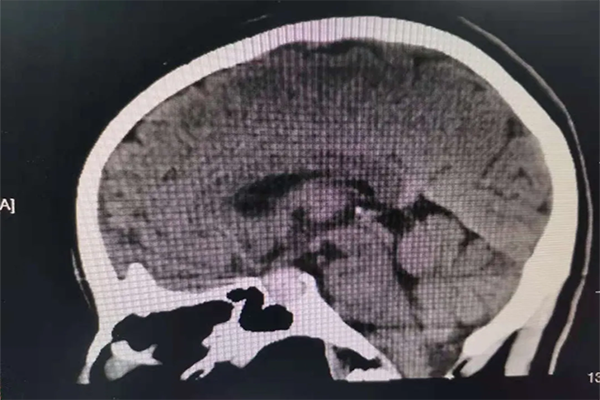

患者段女士,42歲。反復頭暈、眼花、心慌已經5月多了,5月前當地醫院頭顱CT未見明顯異常。1周前患者頭暈、眼花越發嚴重,輾轉多個醫院無果后,患者來到我院內科住院檢查,完善頭顱CT后,發現鞍區占位,考慮垂體腺瘤可能。

當外一科楊金雷主任到達內科時,已經找不到段女士的身影了。楊主任通過查看患者病歷,電腦閱讀CT,診斷患者為垂體腺瘤并出血可能,即患者可能存在瘤卒中。要求立刻打電話讓患者返回醫院接受正規系統的治療。

5個月的時間,CT結果提示鞍區占位病變,進行性增大,考慮瘤卒中可能。

完善檢查后,段女士被確診為無功能性垂體腺瘤并卒中。通過積極術前準備,楊金雷主任帶領的外一科醫護團隊,在省級專家指導及我院麻醉手術室的精誠協作下,為段女士開展了顯微鏡下經鼻蝶垂體腺瘤切除術。手術歷時1.5小時后順利結束。